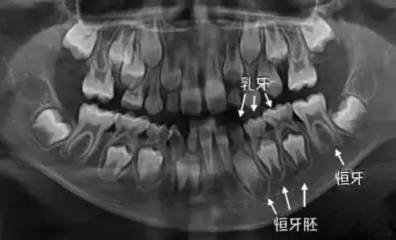

其次,乳牙不及時治療,會(hui) 影響恒牙的萌出和發育。特別是乳牙嚴(yan) 重蛀牙,直接爛掉,細菌殘留,會(hui) 影響下方的恒牙牙胚受到影響,出現恒牙發育不良的情況。